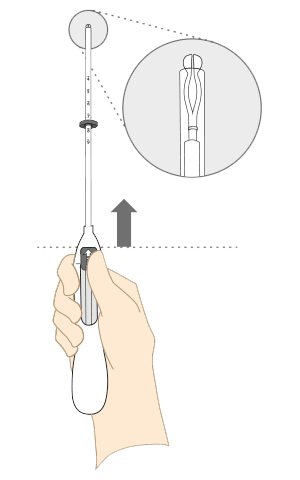

Ta ut eller bytte av Kyleena i noen få enkle trinn

Se hvordan du tar ut Kyleena

Kyleena tas ut ved å trekke forsiktig i trådene med en tang.

Hvis trådene ikke er synlige og systemet viser seg å være i livmorhulen ved bruk av ultralyd, kan den tas ut ved bruk av en smal tang.

Det kan være nødvendig med dilatasjon av cervikalkanalen eller kirurgisk inngrep.

3 trinn for riktig uttak av Kyleena

Hormonspiralen skal tas ut innen utgangen av det femte året

Hvis kvinnen ønsker å bruke den samme metoden, kan ny hormonspiral føres inn umiddelbart etter uttak.

Hvis graviditet ikke er ønskelig, skal uttak utføres innen 7 dager etter første menstruasjonsdag, gitt at kvinnen fremdeles har en regelmessig menstruasjonssyklus.

Hvis hormonspiralen tas ut på et annet tidspunkt i løpet av syklusen, eller hvis kvinnen ikke har en regelmessig menstruasjonssyklus og kvinnen har hatt samleie den siste uken, kan hun være gravid.

For å sikre kontinuerlig prevensjon bør en ny hormonspiral føres umiddelbart inn, eller en annen prevensjonsmetode bør igangsettes.